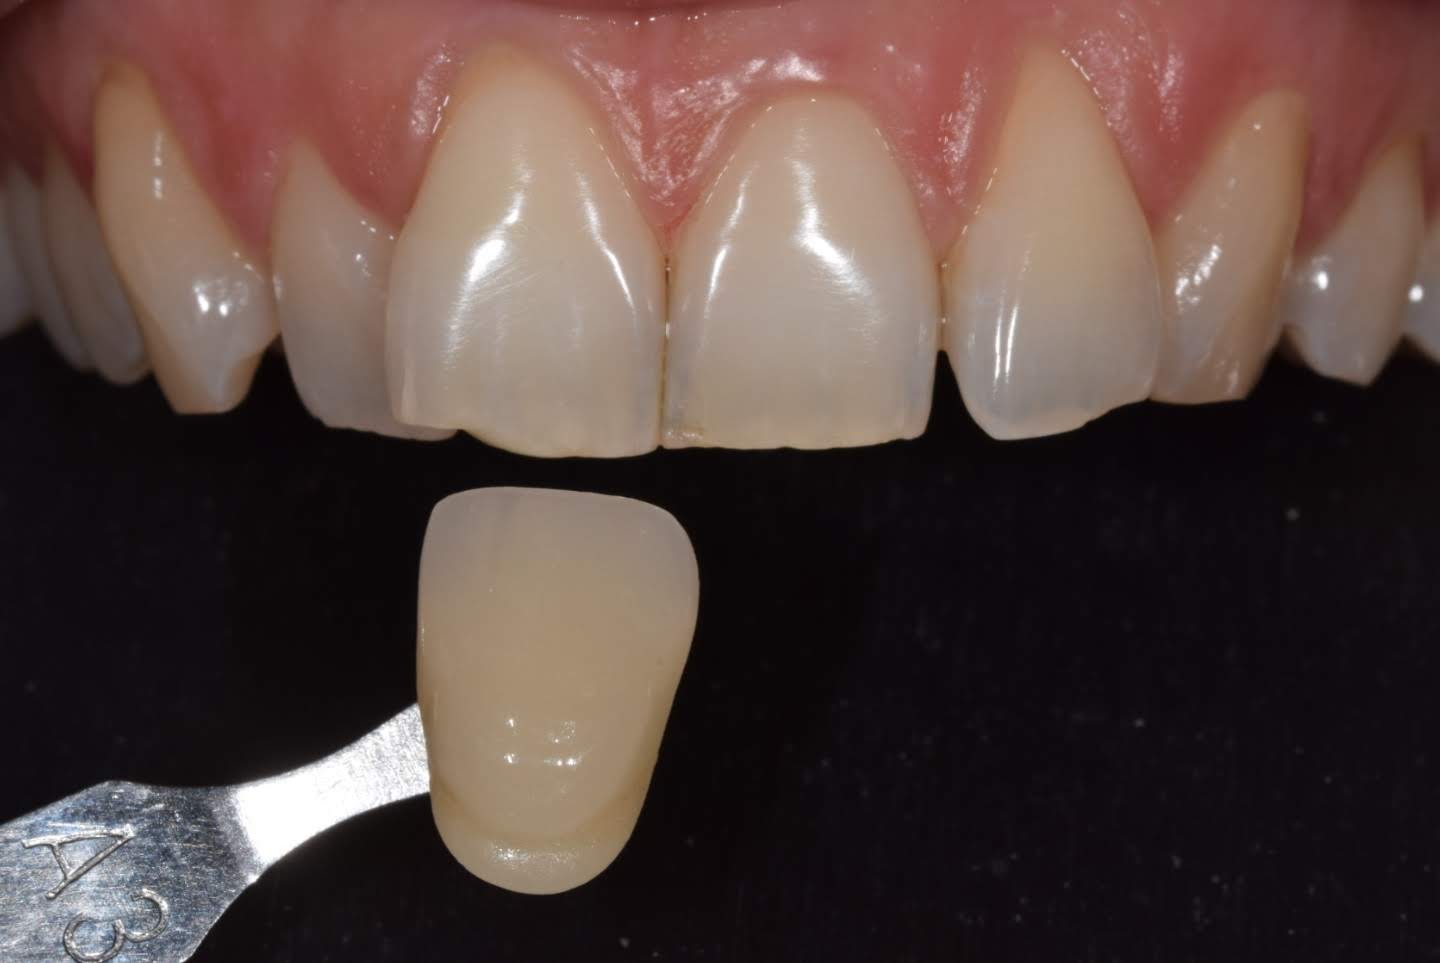

ESTETICA